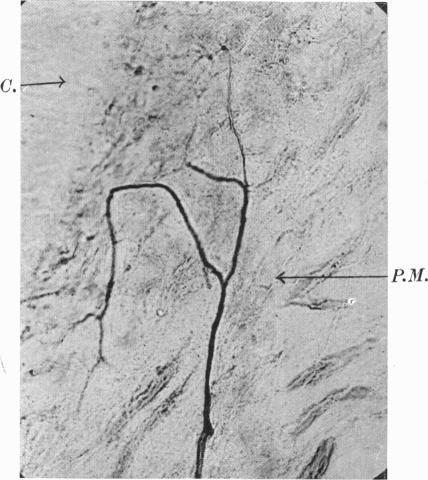

The Innervation of the Periodontal Membrane of the Cat, with some Observations on the Function of the End-Organs found in that Structure.

J Anat. 1937 Jan;71(Pt 2):232-5.